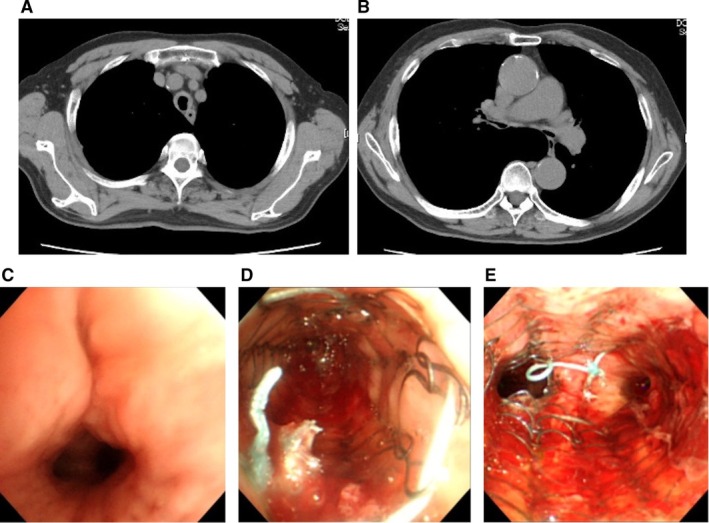

气道支架植入术是处理由恶性和良性条件引起的气道阻塞的关键治疗干预。虽然Dumon y型支架有时适用于广泛气道狭窄的患者,但能够进行刚性支气管镜检查的设备有限。在这种情况下,局部麻醉下通过柔性支气管镜使用多个自膨胀金属支架(SEMS)是一种有价值的选择。我们报告了三个使用这种方法同时放置多个气道支架的病例。病例1为IV期鳞状细胞肺癌患者,其原发肿瘤引起气管外源性压迫并直接侵犯右主支气管。病例2、3临床诊断为气管软化症。在这三个病例中,放置多个SEMS成功缓解了气道狭窄,改善了氧合,减少了呼吸困难,没有出现重大并发症。这些病例支持同时放置多个SEMS作为广泛气道狭窄患者安全有效的治疗选择的潜力。

Airway stenting is a critical therapeutic intervention for managing airway obstruction caused by both malignant and benign conditions. While Dumon Y-stent placement is sometimes indicated for patients with extensive airway narrowing, facilities capable of performing rigid bronchoscopy are limited. In such cases, the use of multiple self-expanding metallic stents (SEMS) via flexible bronchoscopy under local anaesthesia presents a valuable alternative. We report three cases in which multiple airway stents were placed simultaneously using this approach. Case 1 involved a patient with stage IV squamous cell lung cancer, in whom the primary tumour caused extrinsic tracheal compression and direct invasion of the right main bronchus. Cases 2 and 3 were diagnosed clinically with tracheomalacia. In all three cases, the placement of multiple SEMS successfully relieved airway stenosis, improved oxygenation, and reduced dyspnoea, without major complications. These cases support the potential of simultaneous multiple SEMS placement as a safe and effective therapeutic option for patients with extensive airway narrowing.